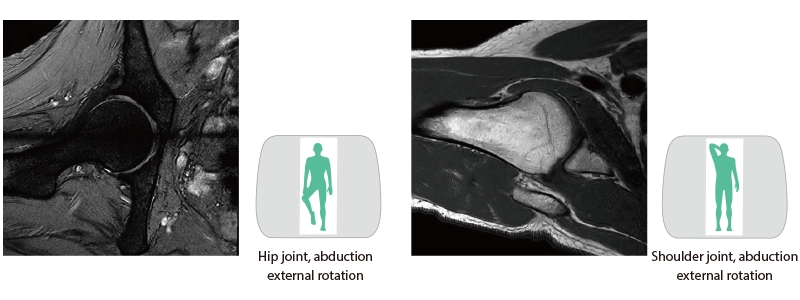

The slice line setting support function, "AutoPose," automatically sets the slice lines as soon as the scanogram is scanned.

Wide bore and variety of coils to support comfortable examinations

The 70cm diameter wide bore improves comfort for patients. To match the wide bore, we also paid close attention to the size of the patient table to ensure a space of 62 cm for the moving part of the patient table. This allows for quick adaption to imaging in a variety of patient positions.

- * Not applicable to all body positions and patients.